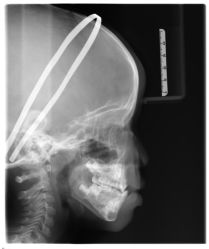

• -青苗儿童口腔(长楹天街购物中心)

相册

晔子_6763 上传于 20-09-20 | 报错